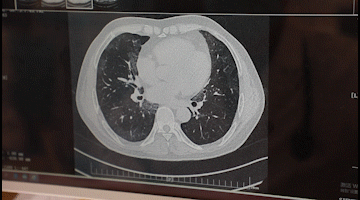

李先生入院后,胸科醫(yī)院吳昌歸院長(zhǎng)、朱運(yùn)奎副院長(zhǎng)組織科室進(jìn)行了深入討論,為其做了詳細(xì)檢查。醫(yī)生先做了導(dǎo)航下氣管鏡冰凍活檢,但病理未獲明確診斷。根據(jù)胸部CT特征、病變過(guò)程治療的反應(yīng),醫(yī)生懷疑是罕見(jiàn)的肺泡蛋白沉積癥。再經(jīng)肺泡灌洗液分析、PAS染色及診斷性分段灌洗后復(fù)查,證明醫(yī)生診斷正確。李先生確診為“肺泡蛋白沉積癥(繼發(fā)性)、肺炎、1型呼吸衰竭,并伴有慢性乙肝、高血脂癥等。

經(jīng)過(guò)4次的治療,李先生沉著于肺泡內(nèi)蛋白樣物質(zhì)漸漸消失,灌洗液為透明色。復(fù)查胸部CT肺部病變明顯吸收。經(jīng)再次灌洗治療后病變完全吸收,恢復(fù)健康。